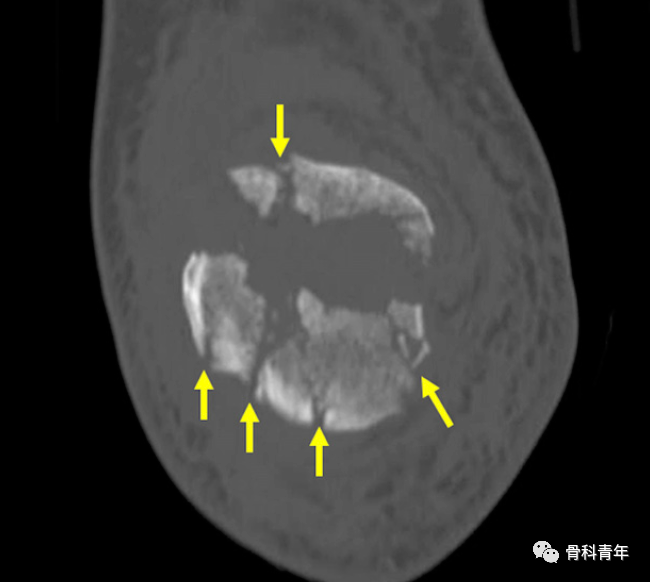

关于髌骨横行骨折,尽管在X线上较多髌骨均可见横行骨折线,但CT检查可发现仅有16%的髌骨骨折为单纯的横行骨折。这提醒我们在复位过程中,不应只关注于横行骨折线的复位,周围的骨折线也应注意到,并精确复位。

CT扫描可见髌骨骨折粉碎,四周骨折线在X线上显示不清晰。